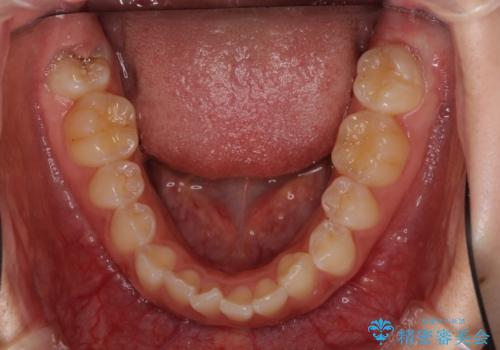

前歯のデコボコを治したい インビザライン矯正治療

- 前歯のデコボコ気になるとのことで来院された患者様です。

下顎骨が上顎骨に対して右側にシフトしており、さらに下顎が後方に位置しているため、非常に強い咬合力で食いしばっている状態でした。

上下顎ともに歯列全体の後方移動とIPR(歯と歯の間を削る)によってデコボコが解消するように設計し、インビザラインにより治療を行うこととしました。

強い咬合力による臼歯部の噛みにくさと、それに伴う歯の移動の鈍さに悩まされ、非常に長い期間を要することとなりました。

上下正中位置は、治療開始時よりは改善したものの、ここが限界であろうというところでのゴールとなりました。

下顎前歯の大半が隠れている状態ですが、左右への歯ぎしりはスムーズに行うことができ、就寝時には後戻り防止も兼ねて、食いしばり対策としてマウスピースの使用を継続するようお願いしております。